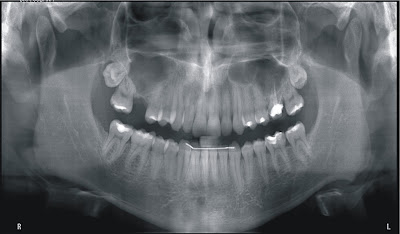

Figura : Radiografia Panorâmica Digital